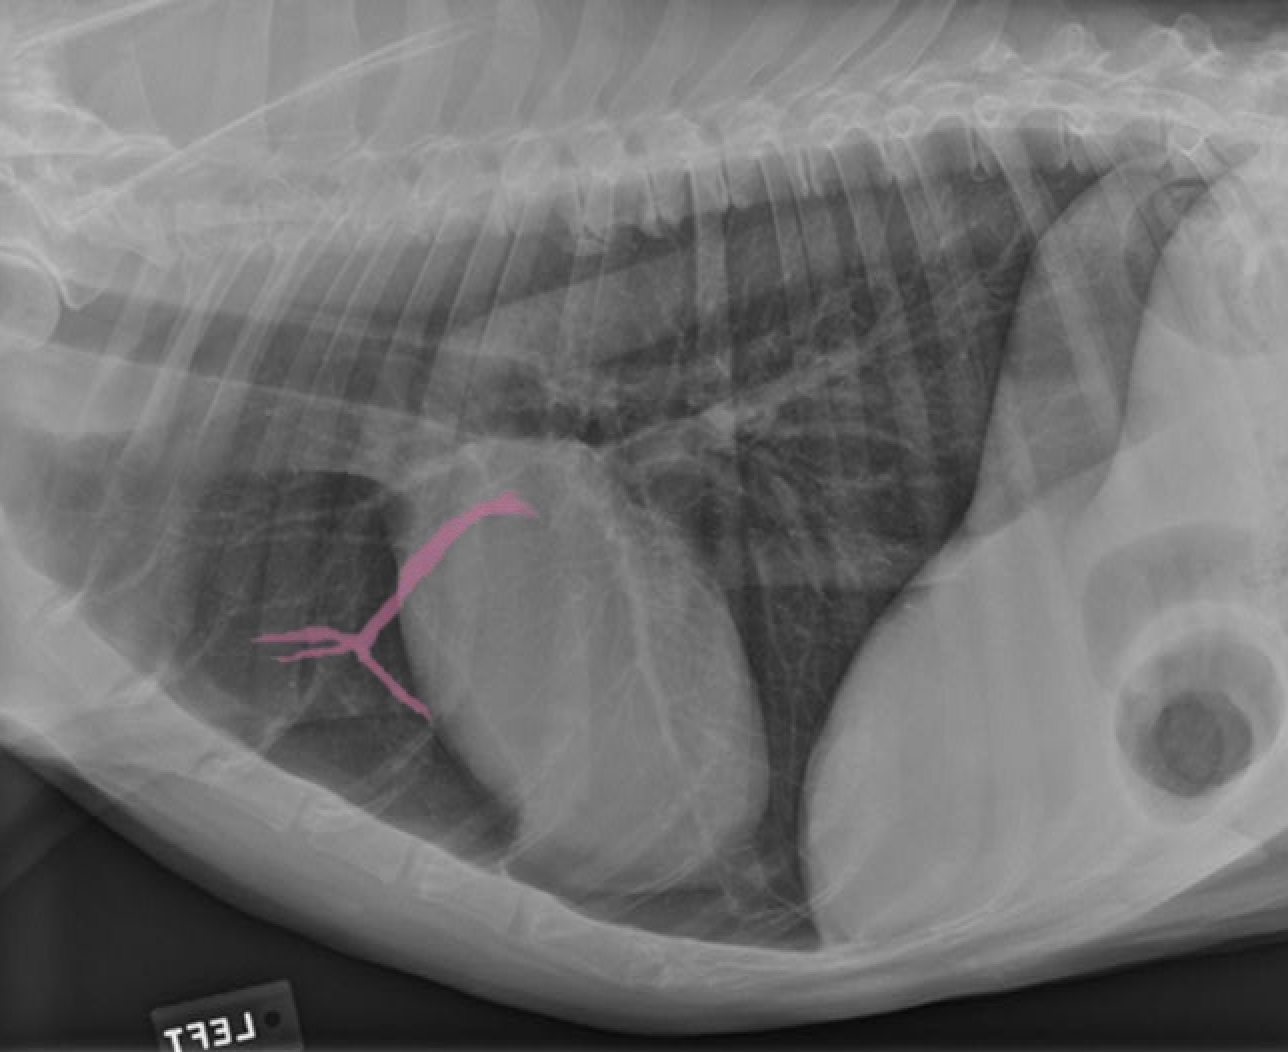

identify the structures

identify the pulomary arteries

identify the aorta

identify the ventral mediastiunum

identify the scapula

identify the ventral lung lobes